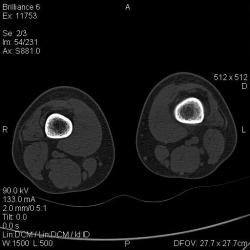

Мальчик 15 лет. Несколько месяцев назад начали беспокоить боли в коленных суставах. Травмы не было. Ребёнку был выставлен диагноз: болезнь Шлаттера, назначено лечение. На фоне лечения отмечалось значительное усиление болей, боли локализовались в левом коленном суставе. При дообследовании выявлена следующая рентгенологическая картина. Наши рентгенологи настаивают на срастающемся переломе. Но: 1) перелом без травмы? 2) бедро так не ломается

Да, на мой взгляд, состояние после обычного "травматического перелома" (трещина), не думаю, что имел место "патологический перелом", так как костная ткань "патологически изменена" минимально. "Перистальная реакция"локальная тоже есть, на КТ "локальная  зона склероза" - все это свидетельствует именно об этом. Хотя в памяти у меня хорошо отложился Ваш последний случай о локальном утолщении кортикального слоя, когда "яйца в гнезде" еще не было. То, что анамнестически "травмы не было" - ничего не значит. Вы, по всей видимости, тоже часто встречались с такими случаями, когда ребенок не акцентировал внимание на "травме", как таковой, хотя клиника есть, боль есть. Конечно, рентгенограммы - не дай бог - ни скиалогии, ни структуры.

Буквально заключение гистологов передать не могу (мой недочет, нужно было сразу выложить на сайтОй-ой-ой), но приблизительно помню - данных за специфический процесс нет, картина консолидирующегося перелома.

Так что, по всей видимости, это действительно был стресс-перелом. Который крайне редко встречается. Хоть статейку в журнал пишиУлыбаюсь.